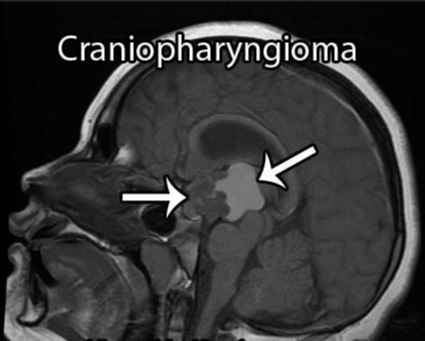

颅咽管瘤可从垂体-下丘脑轴的任何一点发生并沿此轴发展,肿瘤可从位于蝶鞍到大脑的三脑室,大约50%的肿瘤起源于三脑室底水平的漏斗和/或灰结节区域,主要向三脑室发展。患者可出现头痛、视力损害和由中枢性尿崩症导致的多饮多尿等症状,儿童可出现发育迟缓,成人可出现性功能障碍和下丘脑综合征(如体温调节紊乱、水电平衡紊乱)。

颅咽管瘤病变的起源及部位决定它周围的重要解剖结构,包括视神经、垂体柄、下丘脑、还有颈内动脉的分支,基底动脉的分支,基底动脉、后交通动脉和大脑后动脉跟肿瘤的关系可能会密切,此外还有脑干等。视神经跟视力有关系,垂体柄跟内分泌有关系,下丘脑决定病人认知能力和术后内分泌功能,脑干则是人体的“生命中枢”,颈内动脉、基底动脉这些大血管总管人体血液运输,手术切除过程中一旦损伤这些重要结构,可能导致灾难性、不可逆的神经功能损伤。